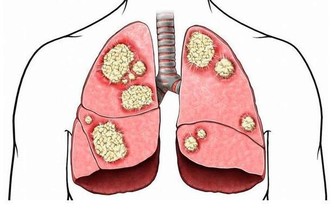

消化系統疾病

腸胃是人體的第二顆大腦,主要由三大激素共同參與胃腸道功能,包括胃泌素在內,荷爾蒙失調時,容易引發腹部疼痛、消化功能紊亂的的原因即在此。